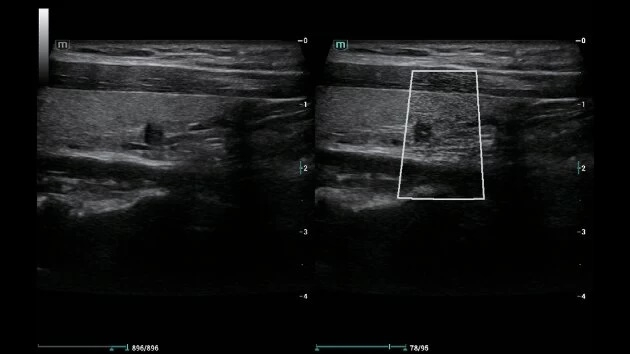

• Высокочувствительная технология HR Flow для детальной визуализации кровотока

HR Flow:

Да